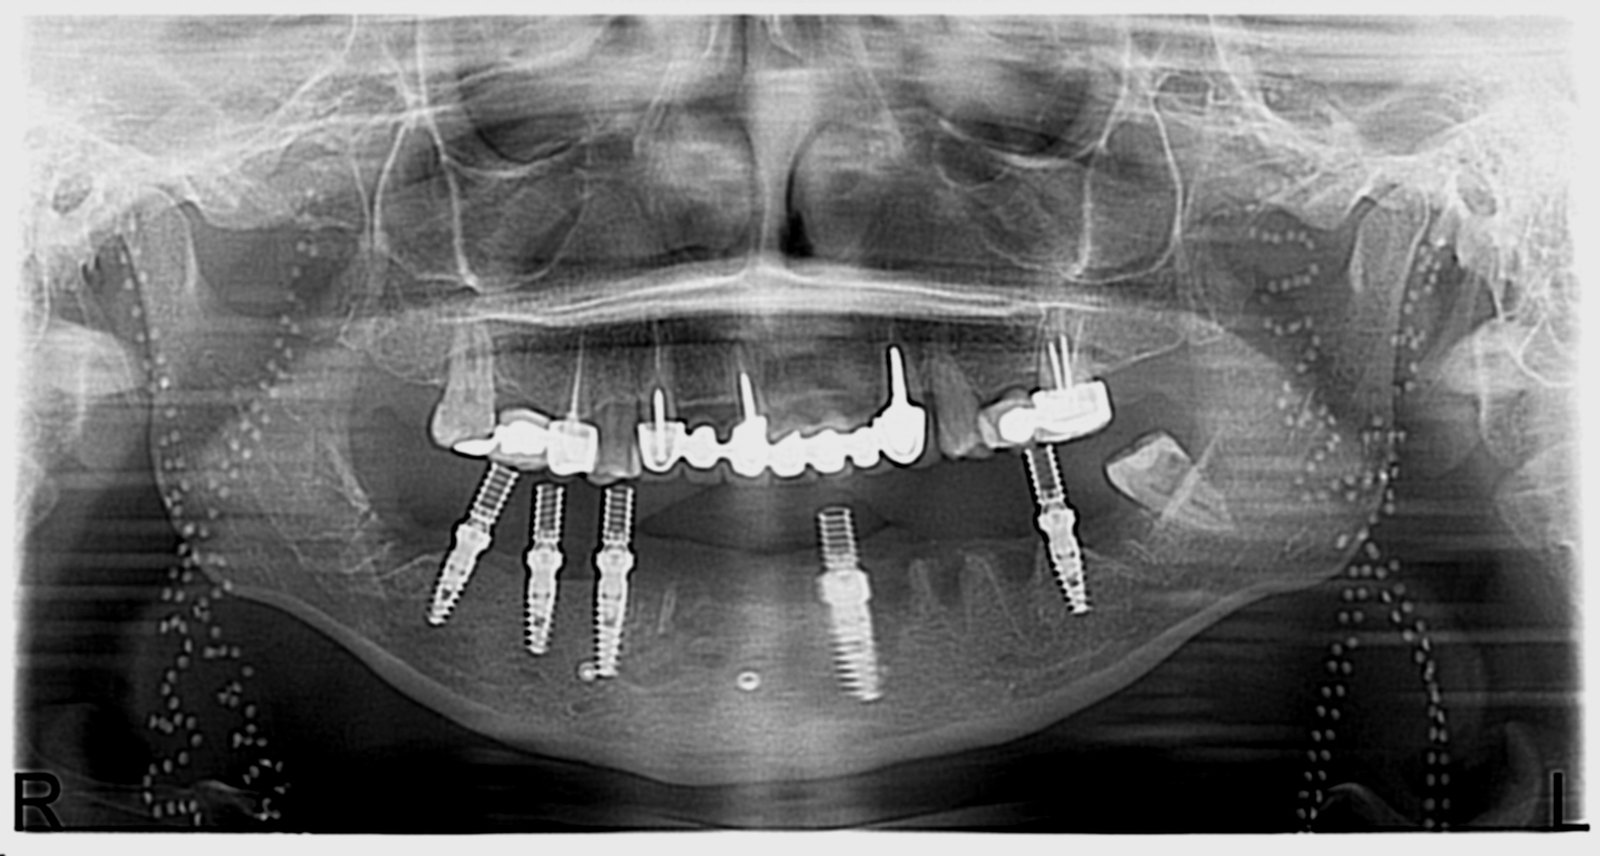

Réhabilitation complète avec mise en charge immédiate (4 implants bas / 6 implants haut)

Le patient se présente avec des dents qui bougent, en haut et en bas.

Nous avons commencé par la mâchoire inférieure avec 4 implants et une mise en charge immédiate.

Trois mois après, le haut a été fait avec le même principe avec 6 implants.

Cette fois-ci, il existait un déficit osseux, résolu par une technique d’expansion sans avoir recours à la greffe d’os.

Les prothèses réalisées sont vissées, ce qui permet de les enlever, les nettoyer une fois par an, ou résoudre n’importe quel problème.